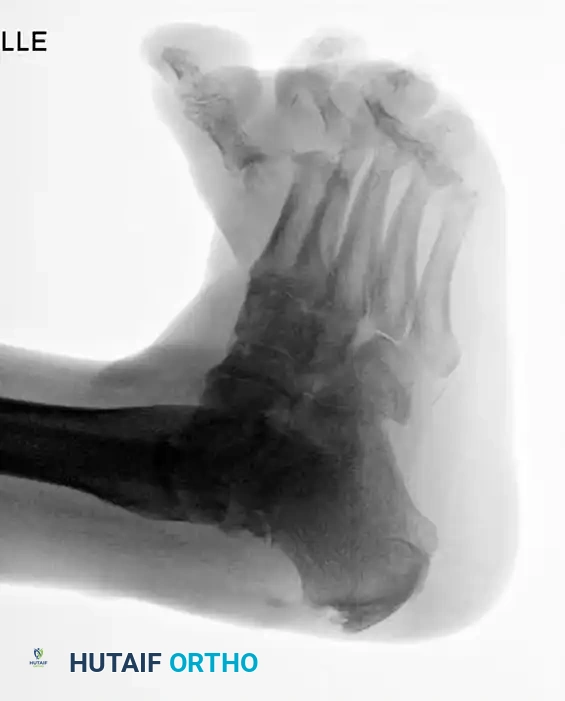

Midfoot and Forefoot Charcot Reconstruction

Charcot breakdown is not limited to the ankle. Midfoot collapse (rocker-bottom deformity) and forefoot destruction are common. Surgical reconstruction in the midfoot often relies on the tension band principle. By placing a robust locking plate on the plantar surface of the midfoot, the hardware resists the immense tensile forces generated during the stance phase of gait.

Image

FIGURE 85-22 A: Preoperative radiograph demonstrating severe Charcot arthropathy of the midfoot with classic rocker-bottom deformity.

FIGURE 85-22 B: Postoperative reconstruction utilizing a heavy plate on the plantar surface, taking advantage of the tension band principle to provide vastly stronger fixation.

Forefoot Charcot arthropathy similarly requires meticulous realignment and often extended fusions or resections to prevent recurrent ulceration beneath prominent metatarsal heads.

FIGURE 85-24 A and B: Radiographic examples of advanced Charcot arthropathy affecting the forefoot, requiring complex realignment to restore a braceable architecture.